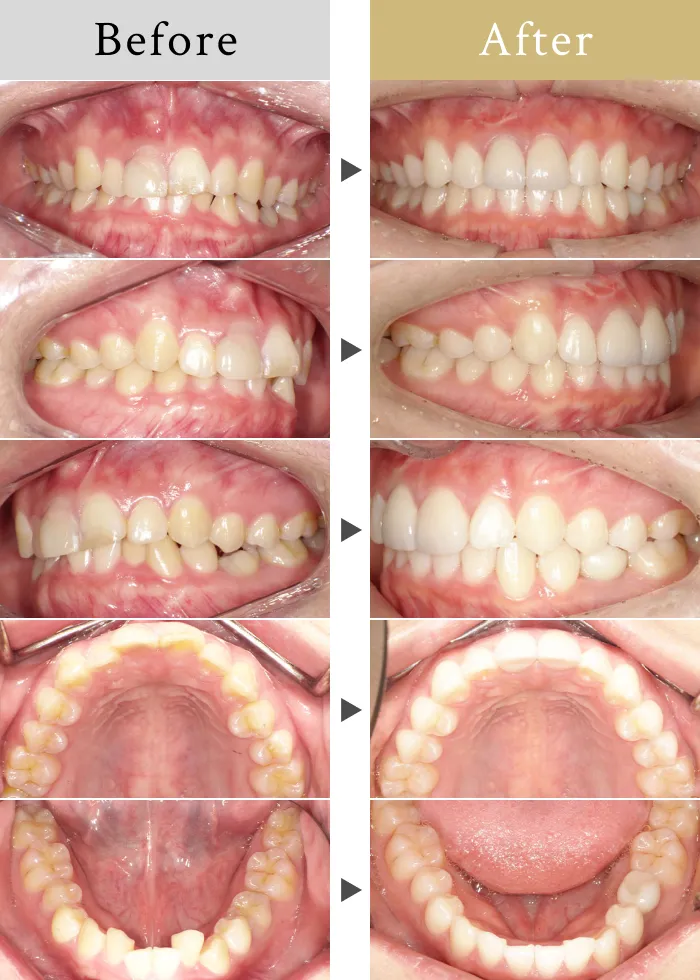

根管治療、インプラント治療と並行したインビザライン矯正で理想的な歯並びに

前歯は神経が膿が溜まっていたので、根管治療して被せものをしていきます。

左下の5番は先天的に大人の歯がなく、子供の歯がぐらついていたので、インプラント治療をします。

噛み合わせに問題があり、上の前歯が前方に押し出されていたので、矯正をして理想的な噛み合わせ、歯並びにしていきました。

82.5万/10ヶ月